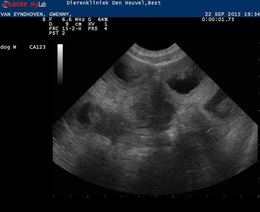

22 September 2015

And then it is time for the ultrasound. We have great news. She is very very very pregnant! We saw a lot of puppies!!

She already showed some signs of pregnancy but still it is always exciting to see if the ultrasound confirms our feeling.

Puppies are expected due 17 October 2015 . Her weight 17,8 kg.

Below you van see two pictures of the ultrasound: